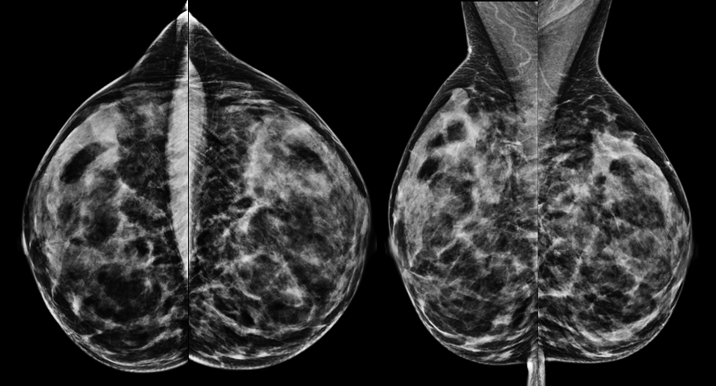

Die Mammographie ist eine Röntgenaufnahme der Brust, mit der gutartige und bösartige Veränderungen dargestellt werden können. Diese Untersuchung ist die einzige anerkannte Untersuchung zur Brustkrebsfrüherkennung und die einzige Methode, mit der auch kleine Verkalkungen in der Brust zuverlässig erkannt werden können. Im Rahmen des Mammographie-Screenings werden alle Frauen im Alter von 50-69 Jahren alle 2 Jahre zur Mammographie eingeladen. In diesem Alter tritt Brustkrebs am häufigsten auf, daher ist eine Mammographie hier in jedem Fall empfehlenswert. Darüber hinaus gibt es Hinweise darauf, dass auch jüngere Frauen ab dem 40. Lebensjahr und ältere Frauen (70 Jahre und älter) in bestimmten Fällen von einer Mammographie profitieren. Wenn bei der jährlichen Tastuntersuchung durch den Frauenarzt oder bei der Brustselbstuntersuchung (Tasten) auffällige Befunde erhoben werden, eine verdächtige Flüssigkeitsabsonderung aus der Brustwarze (blutig oder klar) besteht oder eine neu aufgetretene Hauteinziehung oder Rötung auftritt, ist die Mammographie bei Frauen ab 40 Jahren die erste Methode, die zur Abklärung dieser Befunde eingesetzt werden sollte.

Bei der Mammographie entsteht das Bild entweder durch Belichtung eines Röntgenfilms (Film-Folien-Mammographie) oder mit Hilfe eines digitalen Bilddetektors (digitale Mammographie). Beide Systeme erreichen eine ähnliche Bildqualität. Studien haben gezeigt, dass bestimmte Veränderungen (Mikrokalk) etwas besser mit der digitalen Technik dargestellt werden können. In der Universitätsklinik Tübingen sind zwei digitale Mammographie-Systeme installiert, Film-Folien-Systeme werden nicht mehr verwendet. Die zwei zur Verfügung stehenden Mammographiegeräte bieten außerdem die Möglichkeit, eine Schichtbildmammographie, die sogenannte Tomosynthese, durchzuführen. Mit dieser Technik können gutartige Befunde besser von bösartigen Befunden differenziert werden.

Eine weitere Mammographie-Technik, die an unserer Universitätsklinik durchgeführt wird, ist die kontrastmittelangehobene Mammographie. Sie ist – insbesondere, wenn eine Kernspintomographie (s.u.) aus bestimmten Gründen (z.B. Angst in engen Räumen) nicht durchführbar ist – eine hilfreiche Methode, um auffällige Veränderungen in einer dichten Brust, also einer Brust mit viel Drüsengewebe, zu detektieren. Da die Mammographie eine Röntgenuntersuchung ist, sollte sie nur durchgeführt werden, wenn die Untersuchung medizinisch begründet ist, um eine unnötige Anwendung von Röntgenstrahlen zu vermeiden. Jüngere Frauen (vor dem 40. Lebensjahr) sollten daher nicht ohne eine entsprechende medizinische Begründung mammographiert werden. Ab dem 50. Lebensjahr überwiegt der Nutzen der Mammographie deutlich gegenüber den wenig wahrscheinlichen möglichen Schäden durch die applizierte Strahlung.

Mammographie einer 52jährigen Patientin zur Brustkrebsfrüherkennung